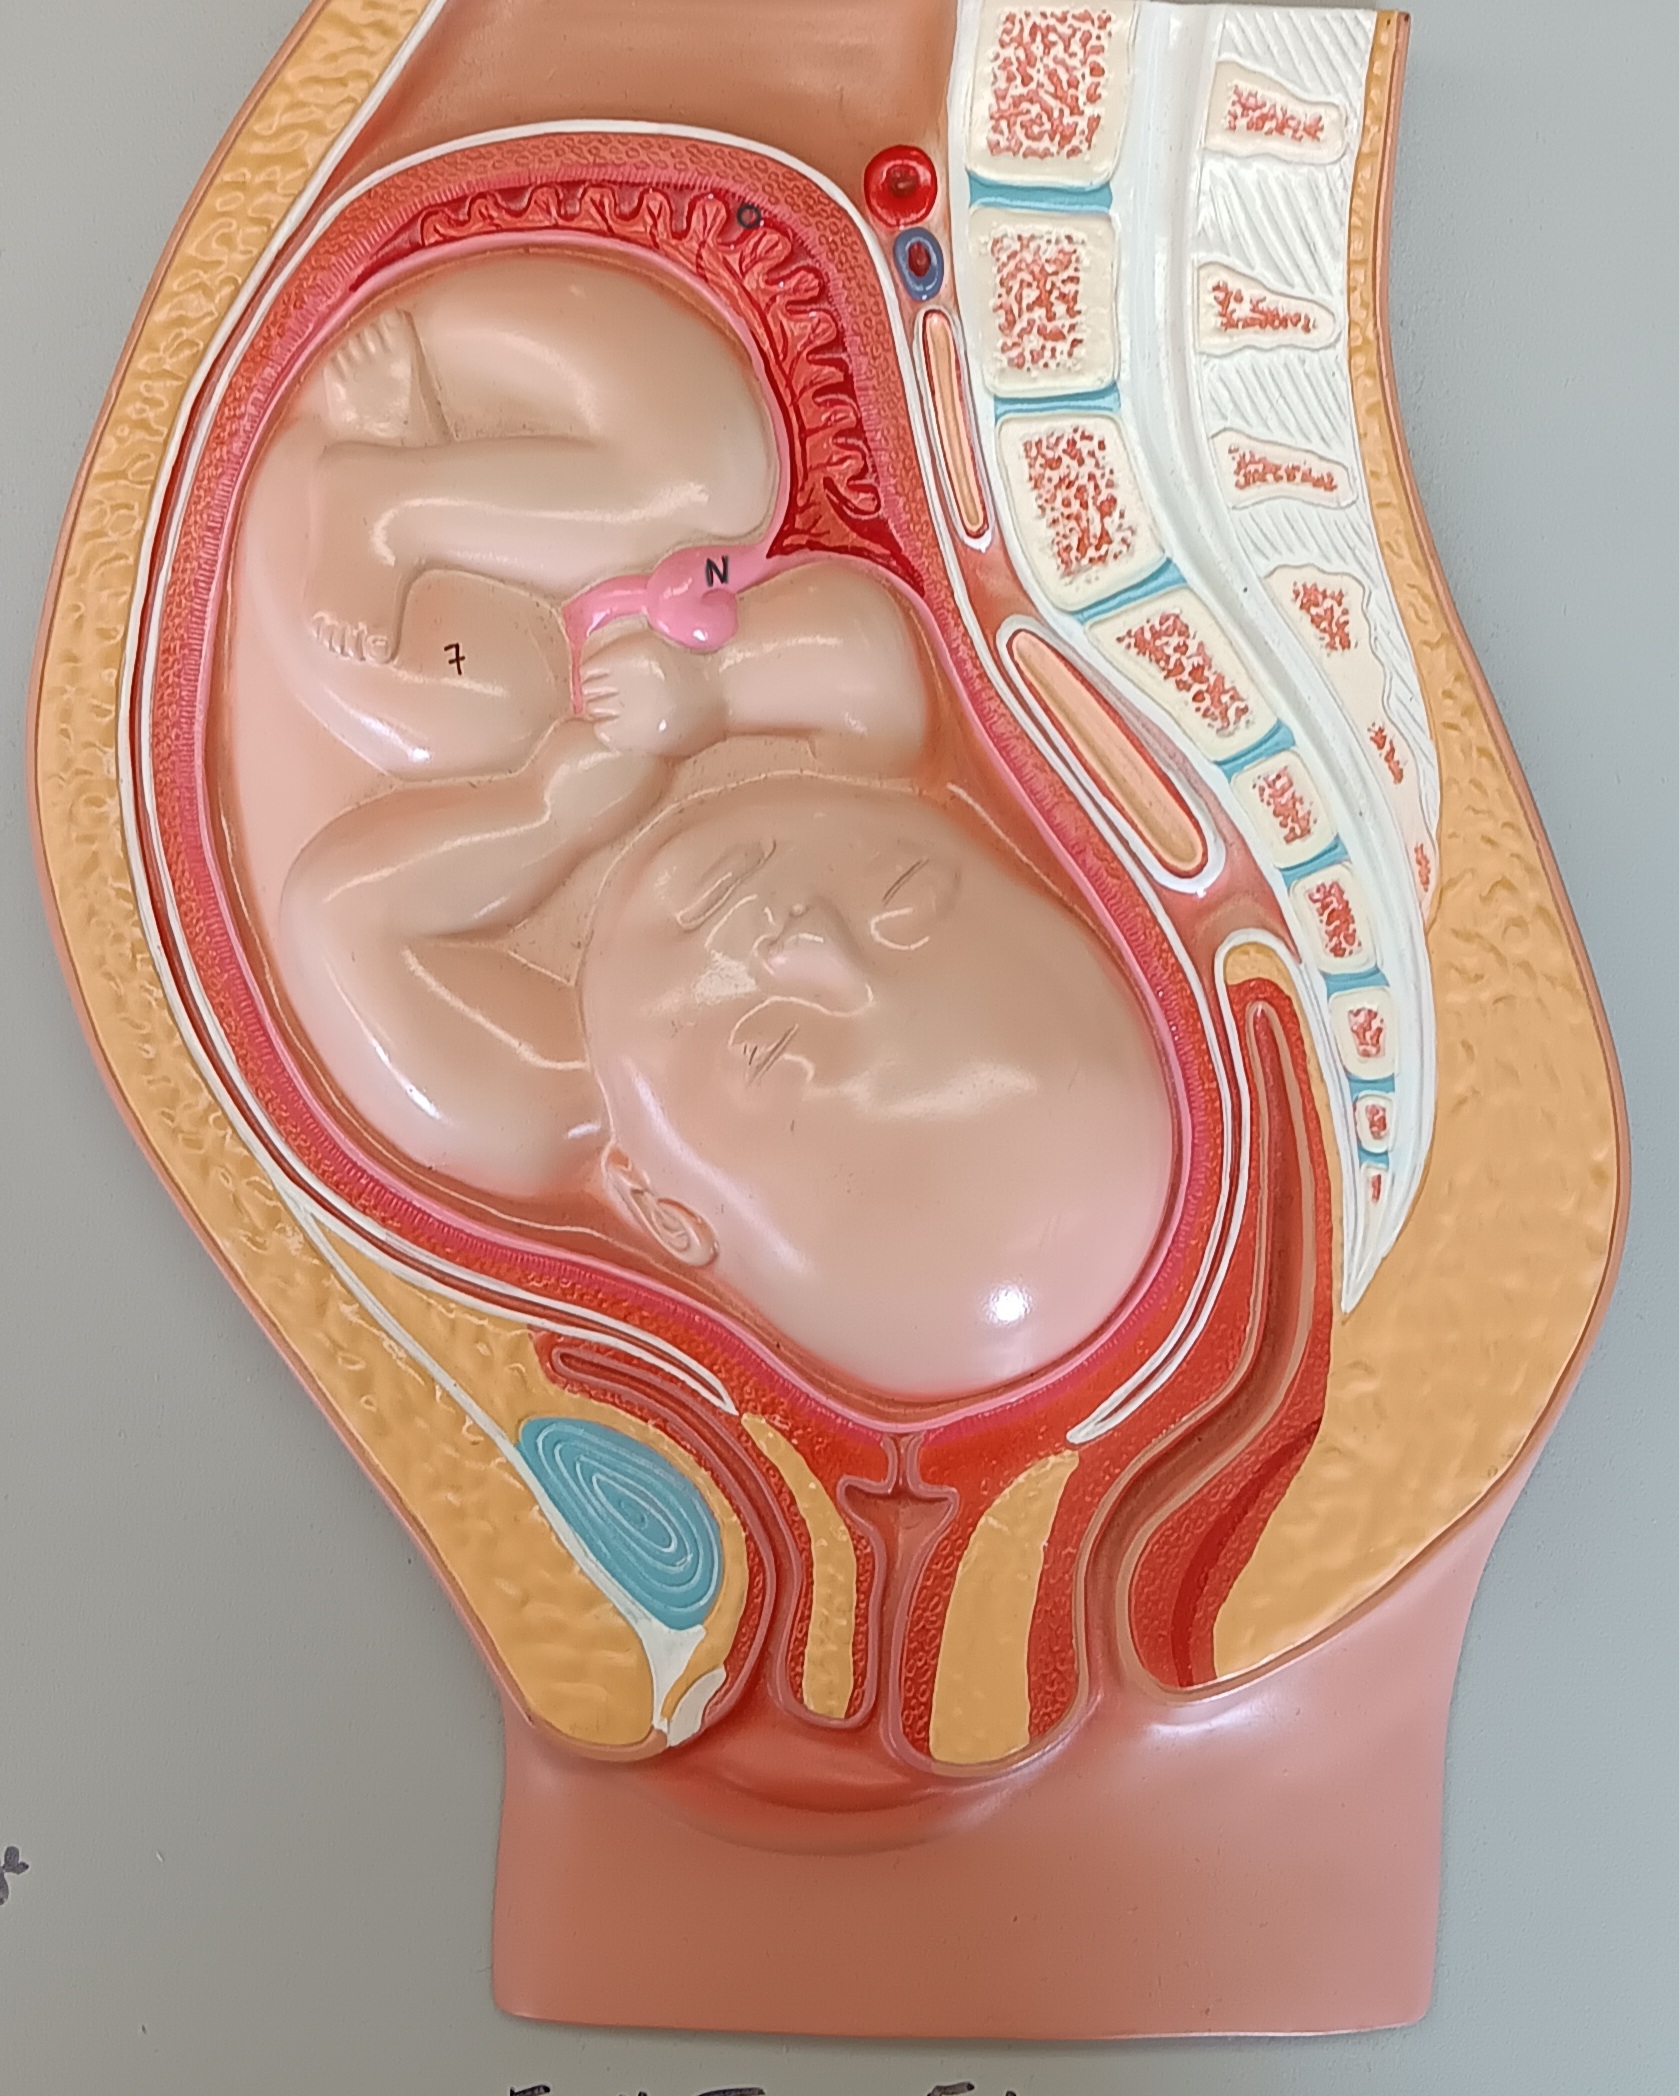

umbilical cord

n

placenta

o